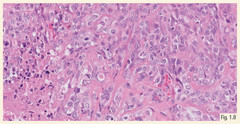

Epiteliodsarcoma定义高等级注意左侧坏死区